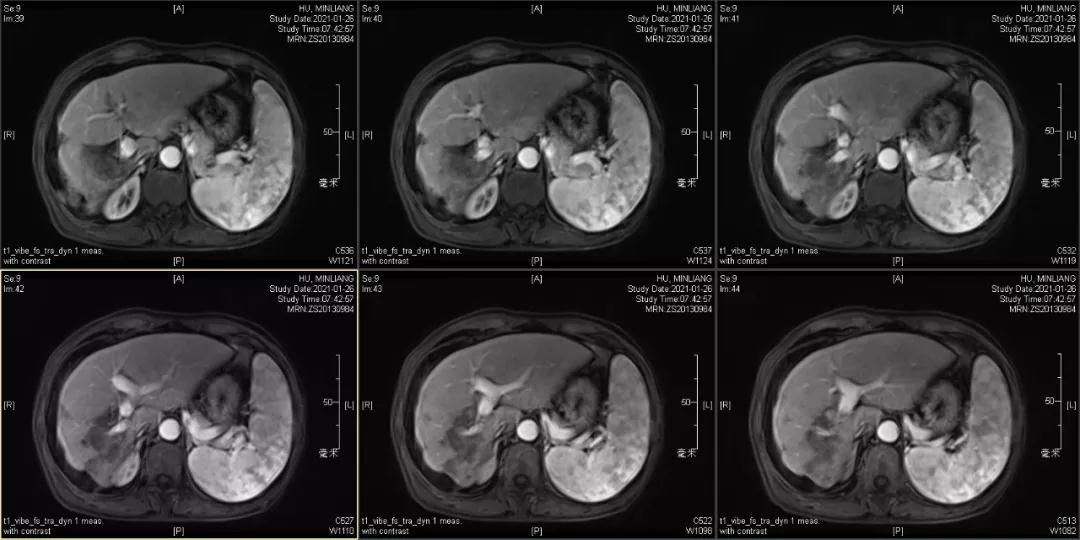

肿瘤学评估(用药后2个月对比6个月):肝内主瘤明显缩小,动脉期强化降低;子灶消失;门脉右支癌栓明显缩小坏死;肺转移灶缩小,大部分消失。

2021-01-25

Δ治疗过程中病灶影像学变化

用药6个月后:肝脏病灶明显缩小,子灶消失,仅有少量动脉期强化;肺转移单个持续缩小稳定,PET CT活性弱;HBV DNA 转阴;可考虑转化切除。